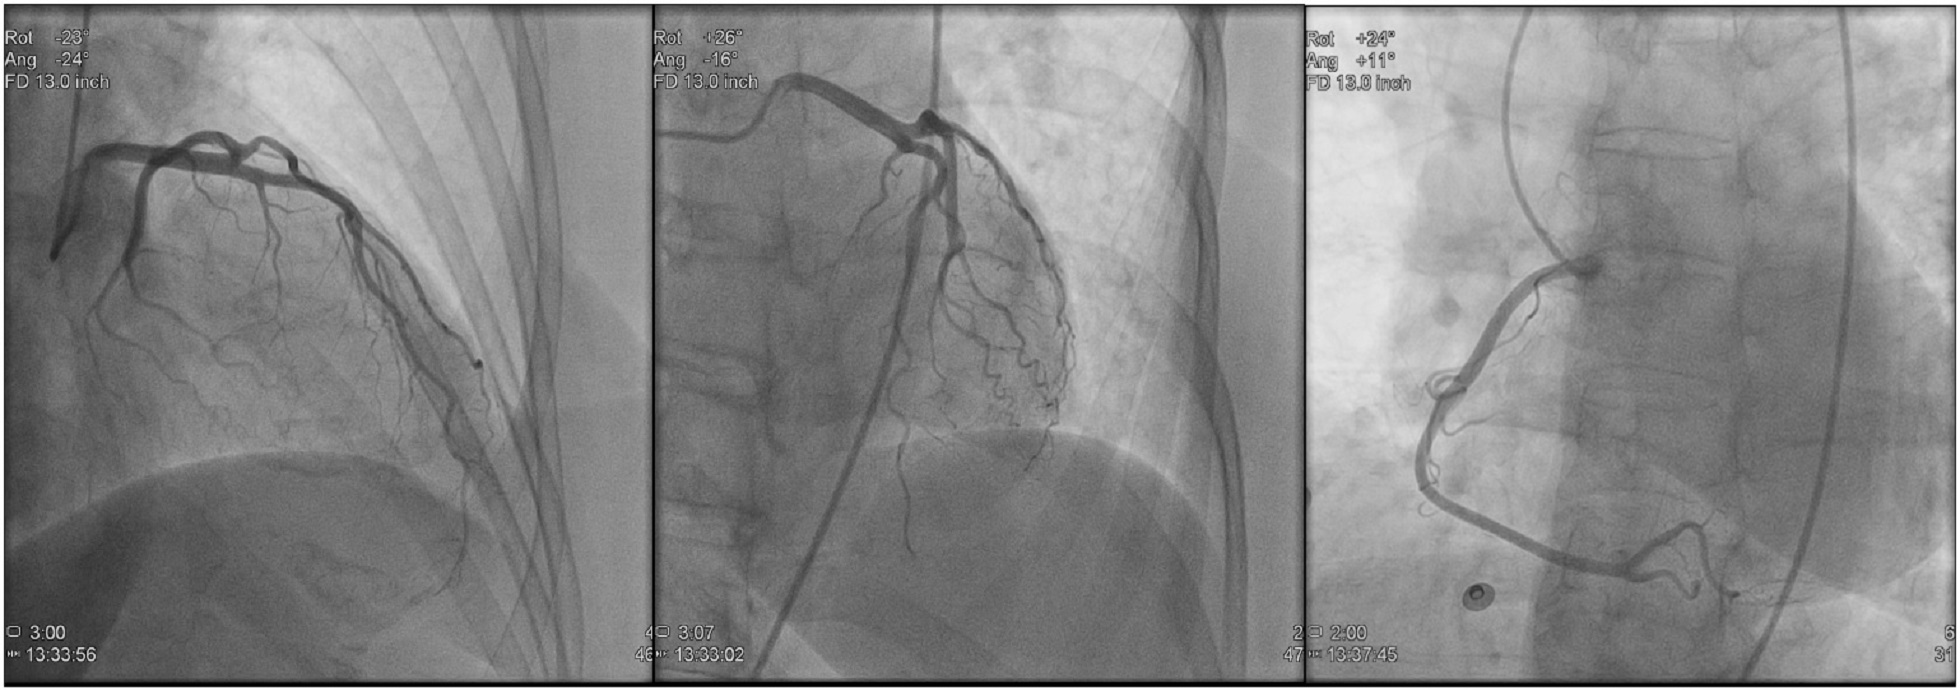

1 CORONARY ANGIO CARDIAC CATH Ablation Procedures Lecture Heart Cath General Anesthesia We performed a review of the role of sedation for cardiac catheterisation, including current practices and summarising available evidence relevant to. Cardiac catheterization (also called cardiac cath or coronary angiogram) is an invasive imaging procedure that allows your healthcare. Most procedures performed in the cardiac catheterization laboratory are done using conscious sedation, with general anesthesia reserved only for the most. Heart Cath General Anesthesia.